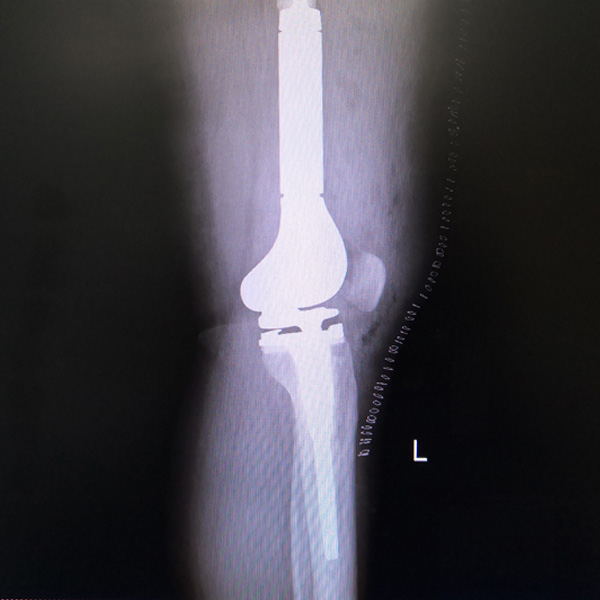

骨肉瘤手術(shù)

患者張某,女,14歲,診斷為“左股骨遠(yuǎn)端骨肉瘤”,當(dāng)?shù)蒯t(yī)院因?yàn)獒t(yī)療技術(shù)和能力的限制,只能考慮截肢手術(shù)?;颊呒覍偻ㄟ^平臺(tái)推薦,指定到哈......